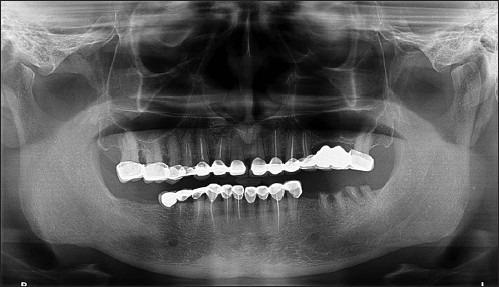

The replacement of missing teeth with implant-borne restorations has become a treatment modality accepted by the scientific community for fully and partially edentulous patients. Recent reports have demonstrated the successful placement of dental implants into the fresh extraction socket in the anterior as well as in molar regions, which is made possible due to modification in implant surface. The present case report highlights the placement of three bicortical screw (BCS) implants into the fresh extraction sockets and one KOS implant in edentulous area with flapless technique. All the implants were immediately loaded and followed up for a period of 6 months.

用种植体支持的修复体替代缺失牙已成为科学界认可的针对全口和部分牙列缺失患者的一种治疗方式。近期报告显示,由于种植体表面的改良,已成功将牙种植体植入前牙区以及磨牙区的新鲜拔牙窝。本病例报告重点介绍了采用不翻瓣技术将3枚双皮质骨螺钉(BCS)种植体植入新鲜拔牙窝以及在无牙区植入1枚KOS种植体的情况。所有种植体均即刻负重,并随访6个月。